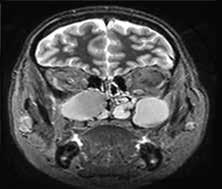

Physical examination revealed a firm, palpable neck mass fixated on the right (figure 1, A). Laryngeal endoscopy showed normal vocal fold movement and a projection of the posterior pharyngeal wall. Magnetic resonance imaging (MRI) revealed an 11-cm mass extending from the right to the left sternocleidomastoid (SCM) muscles (figure 1, B). Surgery was scheduled, with the goal to resect as much tumor as possible and to refer the patient for postoperative radiotherapy.

Figure 1. A: Photo shows the appearance of the neck, with enlargement of the right side and obliteration of the space between the sternocleidomastoid muscle and the larynx. The scar of the previous thyroidectomy is visible. B: T2-weighted MRI of the neck reveals the tumor occupying the space between the larynx and the spine and extending between the large vessels on both sides. The right carotid is enclosed within the tumor.

Figure 3. T1-weighted MRI of the neck 2 years after surgery reveals no presence of tumor.